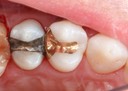

Mark Chun #2 & 3 pre-op

Mark Chun #2 & 3 amalgam removal

Mark Chun #2 & 3 caries removal

Mark Chun #2 & 3 prep